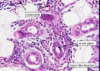

pemphigus vulgaris

40-60 yo

cutaneous erosions/oral ulcers

intact blisters are rare

Painful! Not itchy

Upper trunk and head

+nikolsky

Rx CTSD, immunosuppression

pemphigus vulgaris

40-60 yo

cutaneous erosions/oral ulcers

intact blisters are rare

Painful! Not itchy

Upper trunk and head

+nikolsky

Rx CTSD, immunosuppression